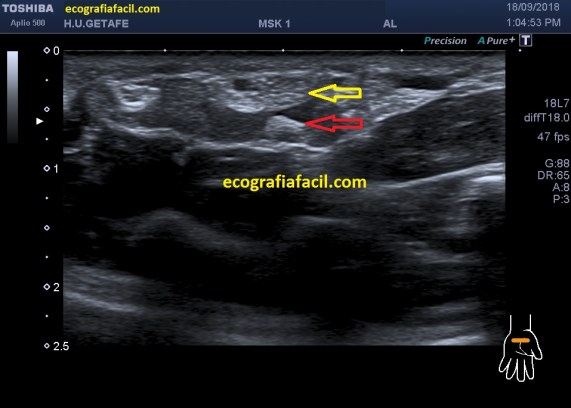

En el protocolo de exploración testicular te contaba cómo había que hacerlo y la semiología normal habitual.

Tenemos que tener claro que el testículo debe verse hiperecogénico y homogéneo y partiendo de esta premisa, realizar los cortes necesarios estudiando la anatomía testicular, incluyendo siempre, testes, epidídimo, cubierta y paquete vascular, es decir, dentro de la bolsa escrotal no nos dejamos nada sin ver.